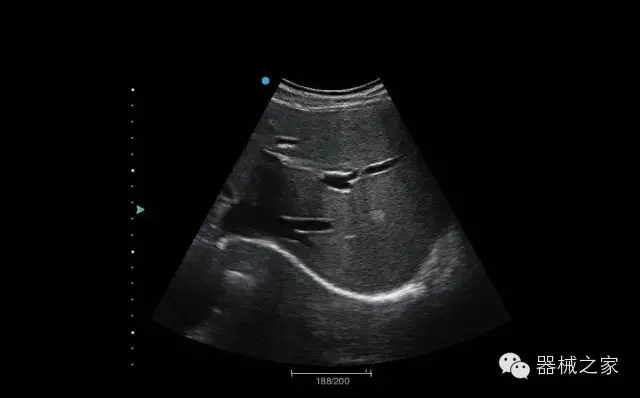

臨床圖片賞析

頸動脈頻譜